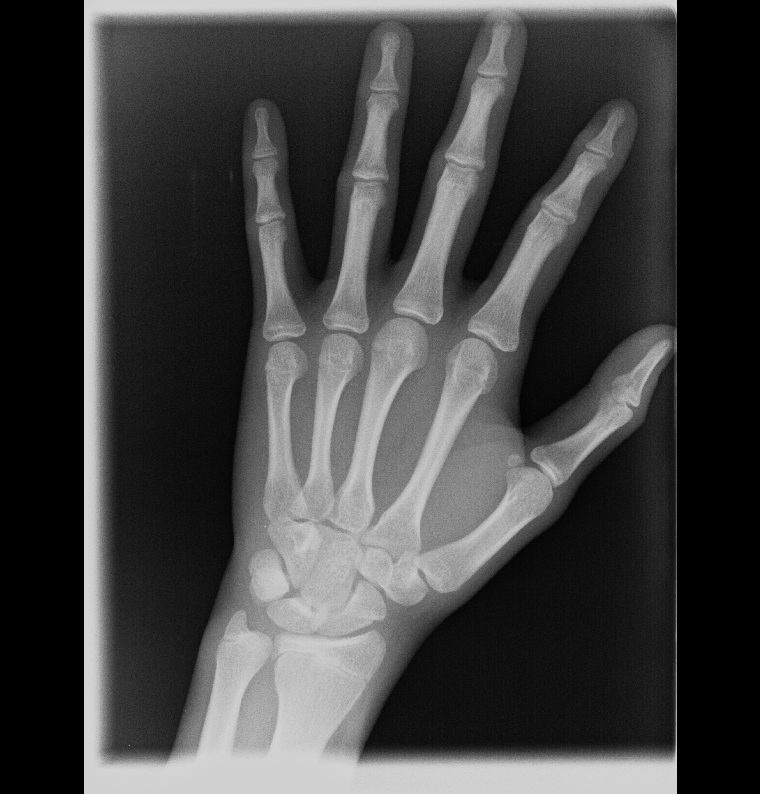

Your phalanges (fingers) are fused

Metacarpals are fused too

And your distal radius and ulna (wrist) are fused too, which are the last bones too fuse and close at an average age of 18-19 which suggest that your skeleton has reached adult maturity

So HGH or anything else, or anything else (except Limb Lengthening Surgery) will not work